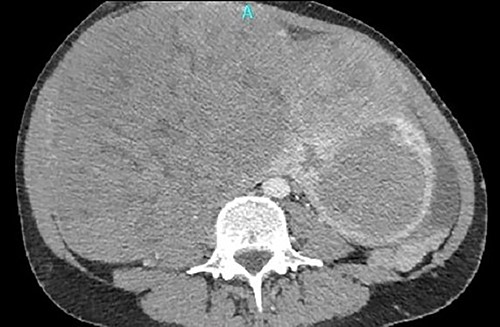

Under fluoroscopy, an aortic occlusion balloon catheter (Reliant AB46 Medtronic Minneapolis, SENSH 1228 W) through a 12F introducer sheath was inserted to the right internal jugular vein into the IVC and was positioned in the restricted free inferior caval space just below the renal veins (Fig. 3). Before the final placement of the balloon and the initiation of any surgical procedure, the hemodynamic condition of the patient was checked during the placement and extension of the balloon. No hemodynamic instability was observed, so the operation proceeded to the next step. The catheter balloon was inflated with the appropriate volume of physiologic saline solution to occlude the IVC and the operation began. The temporal vena cava occlusion continued until the fibroid mobilization and the proximal control of the thrombosed left common iliac vein. After mass mobilization, the vena cava was checked manually for possible clots within the vein, coming from the common iliac veins, especially from the left one. Following removal of the fibroids with the uterus, the occlusion balloon was deflated and removed without any complication. The blood pressure and heart rate were monitored continuously throughout the operation; no significant changes occurred. A total hysterectomy with bilateral adnexectomy was also conducted.

Under fluoroscopy, an aortic occlusion balloon catheter was positioned in the restricted free inferior caval space just below the renal veins.